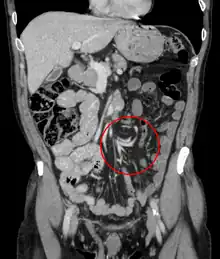

Coronal view of sigmoid volvulus with "whirlpool sign"

CT scan of a small bowel volvulus. It shows two juxtaposed segments of narrowing, which is the spot of mesentery rotation. The other signs indicate strangulation.